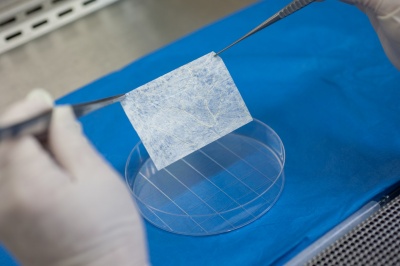

Тканевая инженерия